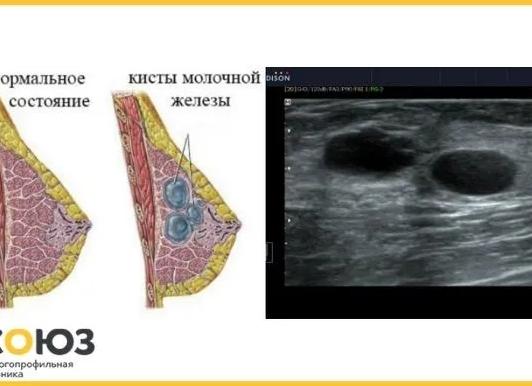

Иногда в УЗИ-заключениях в яичнике – левом или правом врач пишет о наличии анэхогенных образований. Эхогенность – это термин, применяемый в ультразвуковой диагностике для обозначения проводимости тканями ультразвуковых волн. Такие ткани, как кость, полностью отражают ультразвук из-за своей высокой плотности, также он полностью отражается на границе органов и тканей, которые содержат воздух. Плотные ткани сильнее отражают ультразвук, а те, в которых содержится много жидкости, проводят сигнал ультразвукового датчика, усиливая его при этом.